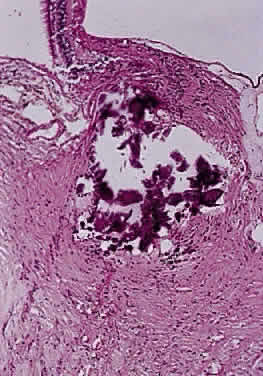

Intraoperatively, hemangioblastoma appears as a reddish, circumscribed tumor that typically is well demarcated from the nerve, although often the central portion is involved. Microscopically, the most striking feature is the abundance of vascular channels, most of which have the appearance of capillaries. Reticulin-staining highlights the vascular network. Between them are stromal cells containing abundant vacuolated cytoplasm, which is due to the presence of lipid. Although bland, the nuclei of the stromal cells are variable in appearance and may exhibit focal marked hyperchromasia (Figs. 46 and 47). Electron microscopy shows that the large stromal cells contain intracytoplasmic particles of lipid and glycogen. Scattered foci of extramedullary hematopoiesis may be present as a consequence of erythropoietin production by the tumor cells. Mast cells also are often readily identifiable. Small cysts are frequent, and the cyst wall consists of gliosis, in which may be found numerous Rosenthal fibers.

Fig. 46. Hemangioblastoma of optic nerve. Multiple capillary vessels are separated by foamy cells (hematoxylin and eosin staining).

Fig. 47. Hemangioblastoma of optic nerve. Foamy cells are a prominent feature between the thin-walled capillary vessels (hematoxylin and eosin staining).